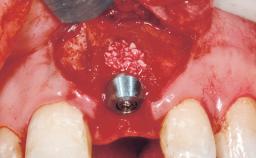

A 30-year-old female patient was referred to the office for the treatment of tooth 11. Her chief concern at the initial visit was to inquire, “Why is my tooth pink?” Upon clinical examination, it was determined that tooth 11 had a previous history of trauma and that the clinical crown had become noticeably pink in color as a result of internal resorption. This diagnosis was confirmed radiographically, indicating a large radiolucency involving the central and distal portions of the clinical crown. It was determined that restoration of this tooth was not possible, and that extraction was indicated. The presence of a mid-line diastema, which the patient wanted to reproduce, directed the treatment plan for tooth replacement utilizing a dental implant.

Placement Protocol Immediate implant placement

Tooth Site Maxillary incisor or canine

Socket Morphology Single-root socket

Socket Integrity Sufficient, with intact bone walls

Bone Volume Sufficient, with intact walls